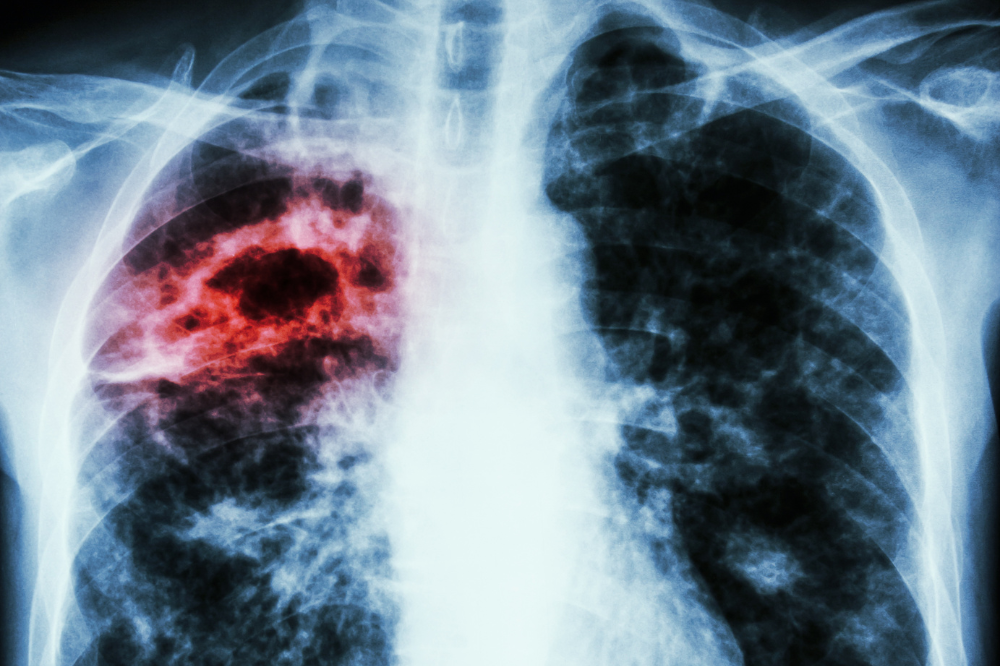

En específico, la biofarmacéutica señaló que el cáncer pulmonar en etapas tempranas puede tratarse mediante cirugía o radioterapia, lo que mejora significativamente la supervivencia.

Destacó también que la combinación de quimioterapia y radioterapia en etapas intermedias puede reducir entre 10 y 20 % el riesgo de muerte, además de elevar la supervivencia global a tres años en un 5,7 %.

“Los planes médicos de tratamiento pueden incluir cirugía, radioterapia, quimioterapia, inmunoterapia o terapia blanco; lo importante es aplicar la medicina personalizada y el uso de biomarcadores para elegir la mejor opción para cada paciente”, señaló el doctor Saráchaga.